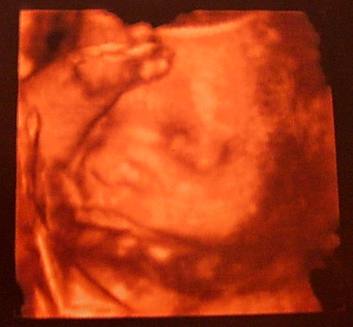

Teszek fel 4 D-s képet.

A nyaka körül az a köldökzsinór, remélem szülésnél nem akarja magát akaszgatni.